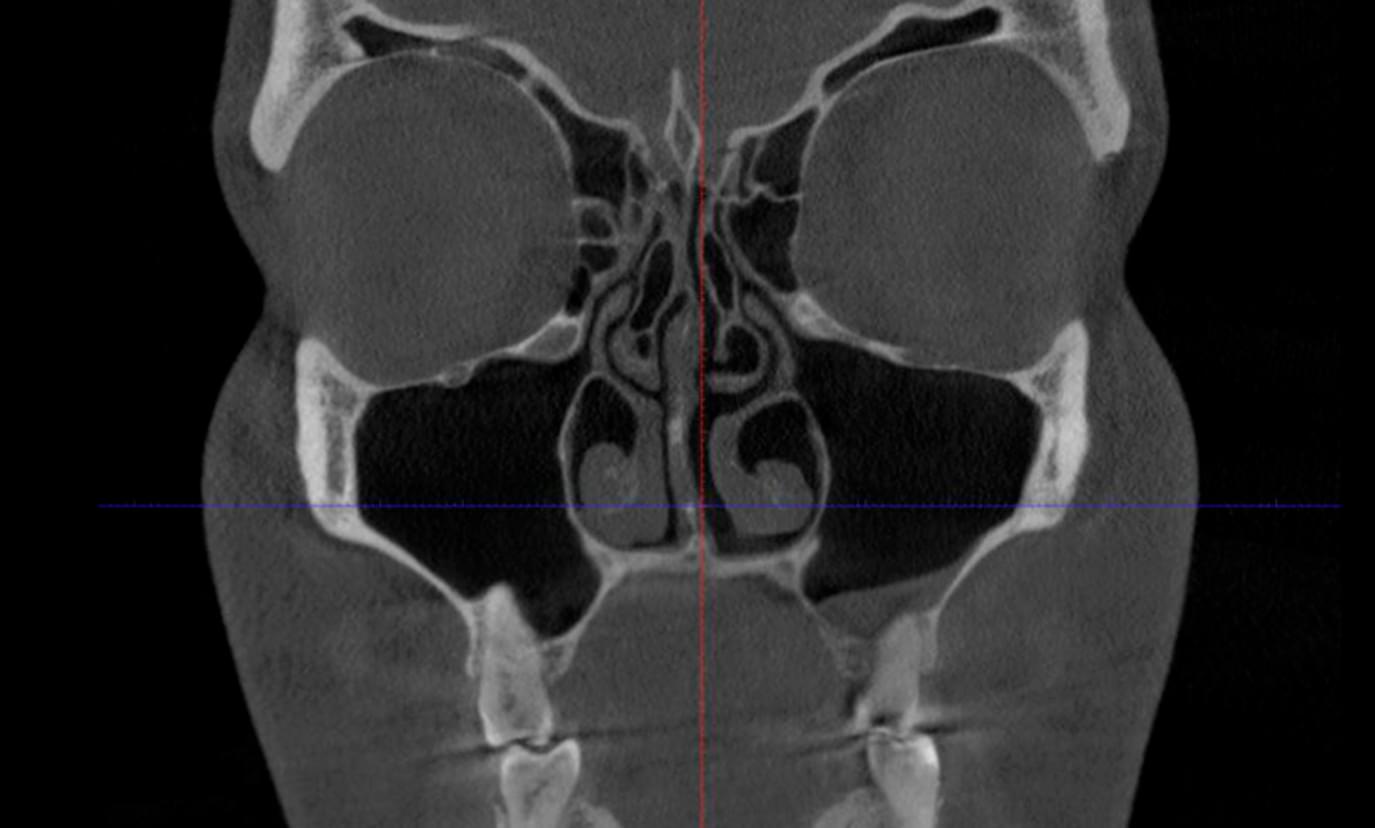

Це «золотий стандарт» діагностики для ЛОР-лікарів та щелепно-лицевих хірургів. Дослідження дозволяє отримати детальну 3D-модель усіх повітроносних порожнин черепа: гайморових, лобних, клиновидних пазух та решітчастого лабіринту. На відміну від звичайного рентгену, КТ показує не просто наявність запалення, а його точну локалізацію, причину та структуру.

✅ Що побачить лікар на КТ двох щелеп?

🔹 "Зубний" гайморит: Чи є корінь зуба причиною запалення в пазусі (одонтогенний гайморит)? Це

часто трапляється, коли корені верхніх зубів проростають у дно гайморової пазухи.

🔹 Приховані патології: Наявність кіст, поліпів, сторонніх тіл (наприклад, пломбувальний

матеріал, що потрапив у пазуху) або грибкових тіл.

🔹 Анатомія носа: Ступінь викривлення носової перегородки та стан носових раковин (гіпертрофія

слизової).

🔹 Заповненість пазух: Рівень рідини чи гною, потовщення слизової оболонки.

🔹 Травми: Тріщини або переломи стінок носа та орбіт.